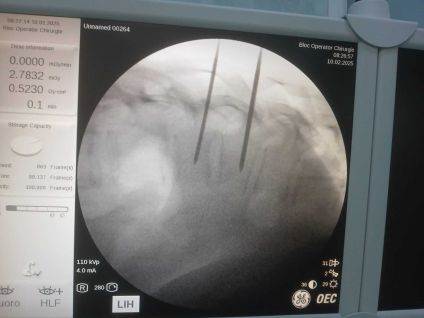

În data de 10 februarie 2025, la Spitalul Județean de Urgență Buzău a avut loc o intervenție neurochirurgicală în premieră. Este vorba despre o intervenție de vertebroplastie percutană, sub control radiologic.

În premieră la nivelul județului Buzău, s-a intervenit neurochirurgical prin procedura denumită „vertebroplastie percutană sub control radiologic”. Operația a durat 30 de minute iar pacienta s-a recuperat complet, cu externare în aceeași zi, post procedural.